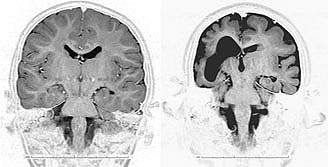

Malformations of cortical development (MCD) are severe abnormalities of the brain's outermost layer, the cerebral cortex, which normally contains complex folds that are densely packed with brain cells. Different types of MCD are recognized based on anatomy. They include microcephaly (small brain and head), schizencephaly (fluid filled clefts in the brain), pachygyria (a cortex with thicker, fewer folds) and polymicrogyria (cortex with many small folds). These conditions reflect a failure of brain cells to grow and reach their proper places during development. Children affected by MCD have severe intellectual disabilities and may not reach developmental milestones.

Brain imaging revealed that the children tended have other types of MCD superimposed with microcephaly. The researchers also found that, in the developing mouse and human brain, WDR62 is enriched in a band of brain tissue that contains neural stem cells.